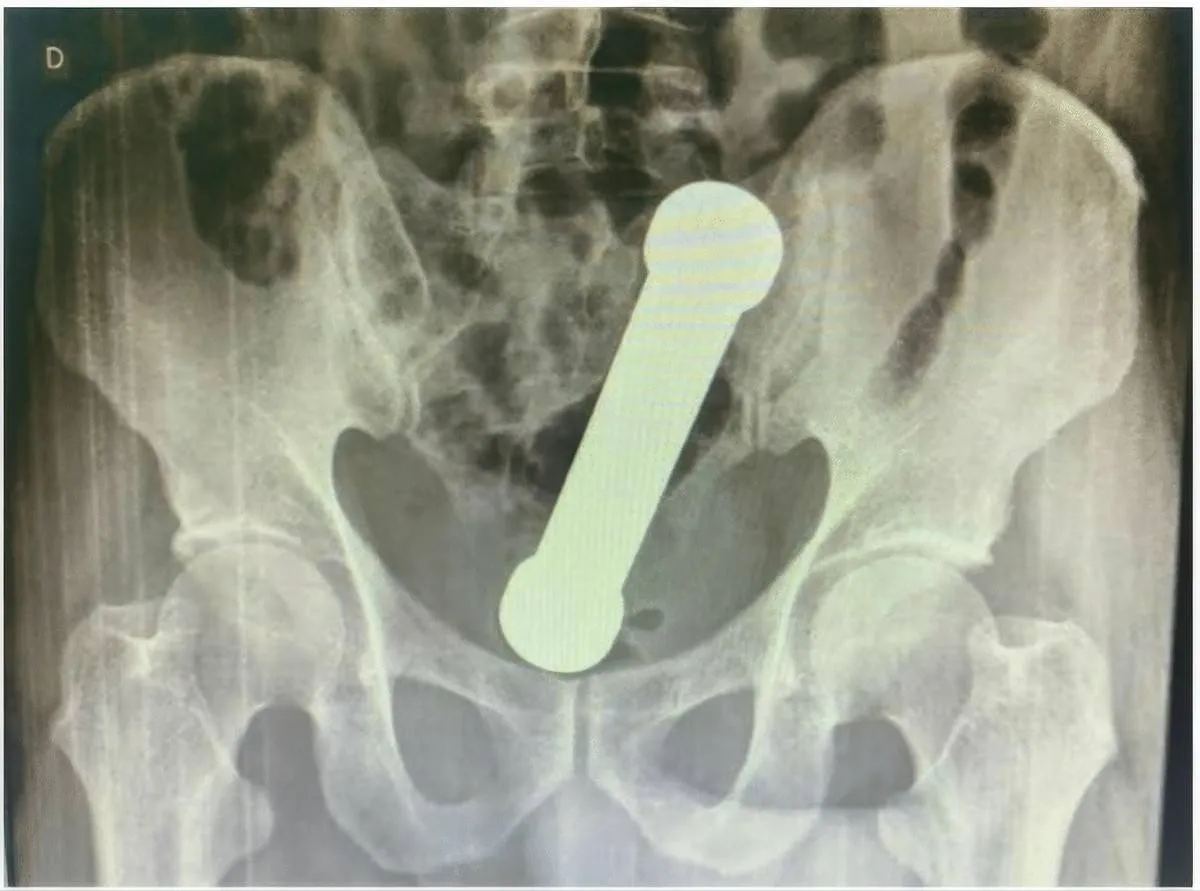

De man meldde zich na twee dagen ellende bij een ziekenhuis in Manaus. Zelf het gewicht verwijderen was hem niet gelukt. Ondertussen kampte hij met krampen, buikpijn, misselijkheid en braken. Niet zo gek, want het ging om een metalen halter van 20 centimeter lang en bijna 2 kilo zwaar. Röntgenfoto’s toonden het object vastgeklemd in de overgang van de dikke darm naar het rectum. Kortom: een “slaapkamerexperiment” dat compleet uit de hand liep.

picture_vk_dumbell_brasil_01

Röntgenfoto van het bekken (vooraanzicht) waarop een vreemd voorwerp (halter/dumbbell) te zien is, ongeveer ter hoogte van de overgang van endeldarm naar dikke darm. (Foto: International Journal of Surgery Case Reports)